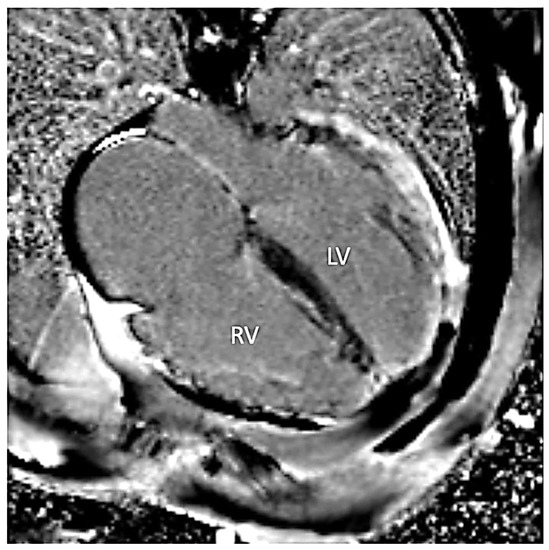

Figure 2.

Steady-state free precession four-chamber image demonstrating enlarged left (LV) and right (RV) ventricles. Additionally, increased myocardial thickness in the septal segments (asterisks) and wall thinning of lateral segments of the left ventricle are seen.